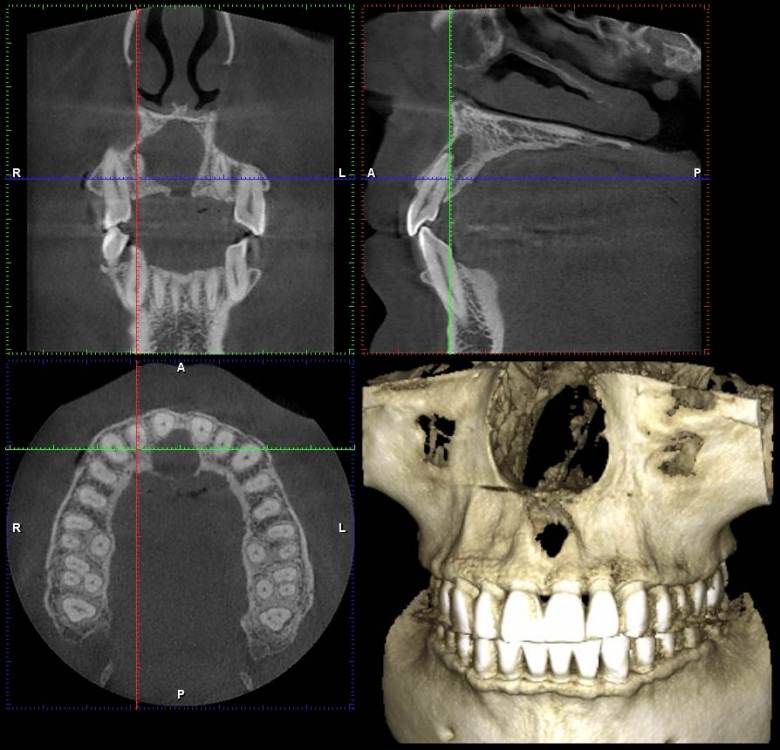

NazranDantist Опубликовано 3 декабря, 2021 Поделиться Опубликовано 3 декабря, 2021 Всем привет. Коллеги, вот такая ситуация обнаружилась на снимке. Со слов пациента, ничего не беспокоит, зубы интактные, травмы не было,холодовая проба положительная. Какую тактику лечения выбрать? Ну и в чем причина? Ссылка на комментарий

Irouil Опубликовано 3 декабря, 2021 Поделиться Опубликовано 3 декабря, 2021 Похоже на кисту резцового канала я бы пошёл на декомпрессию, потом удалил 4 3 Ссылка на комментарий